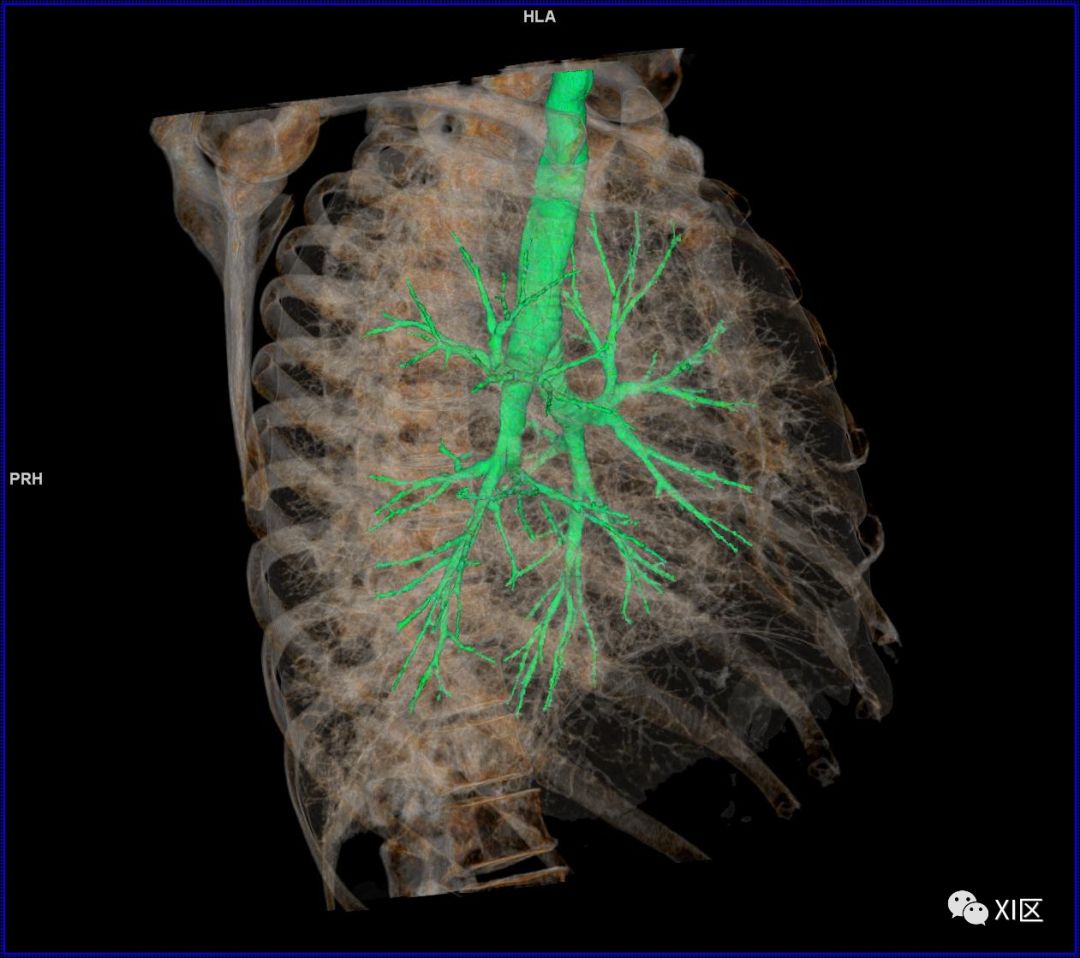

气管支气管树与两肺融合显示

人的支气管(第1级)至肺泡约有24级分支。支气管经肺门入肺,分为叶支气管(第2级),右肺3支,左肺2支。叶支气管分为段支气管(第3~4级),左肺8支、右肺10支。段支气管就是肺的分段的依据。段支气管反复分支为小支气管(第5~10级),继而再分支为细支气管(第11~13级),细支气管又分支为终末细支气管(第14~16级)。从叶支气管至终末细支气管为肺内的导气部。终末细支气管以下的分支为肺的呼吸部,包括呼吸细支气管(第17~19级)、肺泡管(第20~22级)、肺泡囊(第23级)和肺泡(第24级)。 医学百科网 | YxBaike.Com

气管支气管形如树状,因此也称气管支气管树。